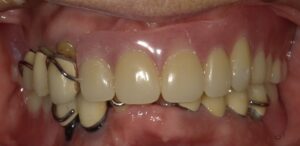

画像は上の前歯を数本同時に抜歯した場合です。

画像が増歯です。通常、増歯は入れ歯を預かって

型を取り技工所に渡して修理する事が基本ですが

そうしますと入れ歯のない期間ができます。

時間はかかりますが診療室でこのように修理することも

可能です。

しかし抜いた後の歯茎が落ち着きましたら

新製と言って作り直した方が画像のように歯の

部分も綺麗に出来上がります。